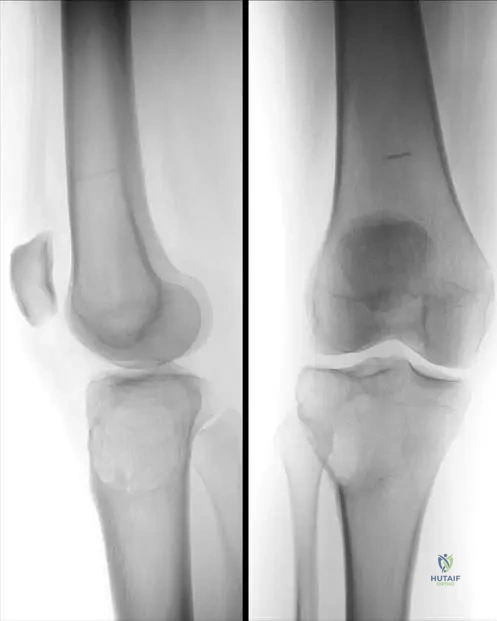

Question 21

A 12-year-old boy presents with multiple palpable bony masses around his knees, shoulders, and wrists. His father and paternal grandfather also have similar bony growths. Physical examination reveals hard, immobile masses protruding from the metaphyses of the long bones, pointing away from the joint. Radiographs confirm multiple osteochondromas (exostoses) arising from the external surface of the bones near the growth plates.

View Answer & Explanation

Correct Answer: C

Rationale: This clinical presentation and family history are classic for Multiple Hereditary Exostoses (MHE), also known as diaphyseal aclasis. MHE is an autosomal dominant disorder caused by inactivating mutations in the EXT1 or EXT2 genes, which encode glycosyltransferases involved in heparan sulfate synthesis. GNAS1 mutations are associated with McCune-Albright syndrome. COL1A1/COL1A2 mutations cause Osteogenesis Imperfecta. FGFR3 mutations cause achondroplasia. TGFB1 mutations cause Camurati-Engelmann disease.

Question 22

A 40-year-old man with a lifelong history of Multiple Hereditary Exostoses (MHE) reports a new, dull ache in his left shoulder, which has been worsening over the past 3 months. He notes that a previously stable exostosis on his scapula has significantly increased in size and is now tender to touch. Physical examination confirms a firm, fixed, tender mass that appears larger than previous assessments.

Rationale: The most serious complication of MHE is malignant transformation of an osteochondroma into a secondary peripheral chondrosarcoma. This risk is estimated to be 1-5% and should be suspected in adults with MHE who develop new pain or rapid growth of a previously stable exostosis, especially in large, axial lesions (e.g., pelvis, scapula). While bursitis can occur, and nerve/vascular compression are possible, the combination of new pain and rapid growth is highly concerning for malignancy and warrants urgent investigation (imaging and potentially biopsy). Pathologic fracture of an exostosis is less common and usually presents with acute pain after trauma.

Question 24

A 6-year-old boy is brought to the clinic because his parents noticed multiple hard, bony bumps around his knees and shoulders. His father has similar bumps. Physical examination reveals multiple palpable, hard masses near the metaphyses of the distal femurs, proximal tibias, and proximal humeri. Radiographs show multiple pedunculated and sessile bony outgrowths arising from the external surface of the bones, pointing away from the adjacent joint.

Correct Answer: B

Rationale: The presence of multiple bony outgrowths (osteochondromas) near the growth plates, often with a family history, is characteristic of Multiple Hereditary Exostoses (MHE). A solitary osteochondroma would not involve multiple lesions. Fibrous dysplasia and enchondroma are intraosseous lesions with different radiographic appearances. Osteomas are typically benign bone tumors of the skull or facial bones, not long bones.